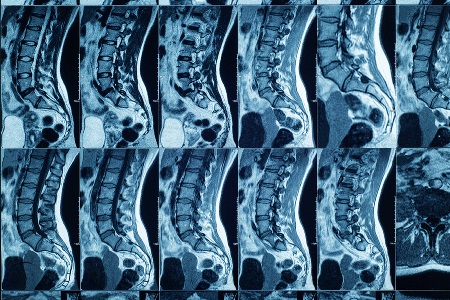

Immagini radiologiche - Cisti di Tarlov

Le cisti di Tarlov (o cisti perineurali) sono sacche piene di liquido cerebrospinale che si localizzano più frequentemente alla base della colonna. Molte sono asintomatiche, ma quando determinano compressione delle radici nervose possono causare dolore radicolare e disturbi sensitivi o motori in alcuni anche invalidanti. Vista la peculiarità e la rarità della condizione patologica, le cisti di Tarlov necessitano di un percorso specialistico sia per la definizione diagnostica sia per la scelta della strategia terapeutica più adeguata che può variare dalla terapia farmacologica, alla riabilitazione neuromotoria fino al trattamento neurochirurgico mirato di decompressione. Fondamentale per le cisti di Tarlov il corretto inquadramento per evitare ritardi nella terapia o scelte terapeutiche non funzionali alla cura.